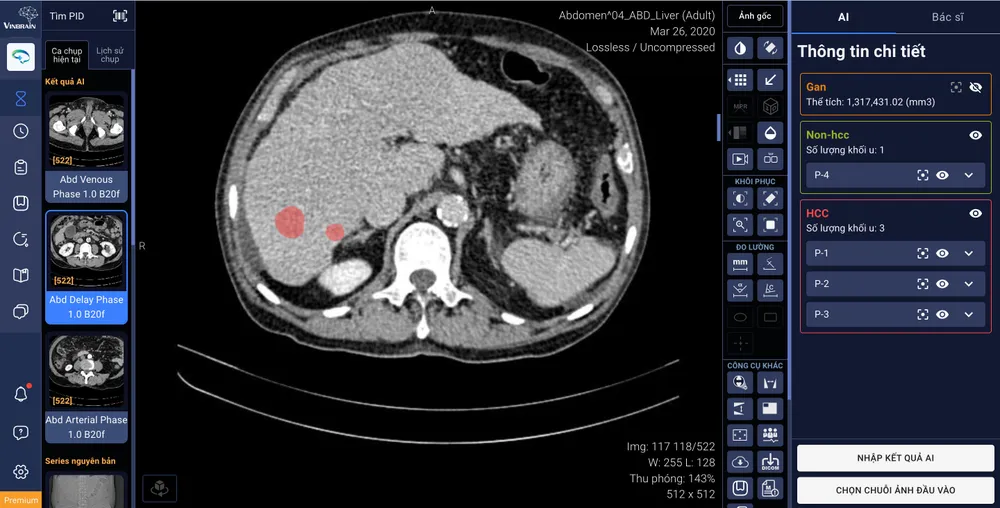

DrAid™ hỗ trợ tính năng tự động khoanh vùng và phân loại tổn thương gan ứng dụng trí tuệ nhân tạo, kết nối trực tiếp với phần mềm quản lý hình ảnh của bệnh viện (PACS)